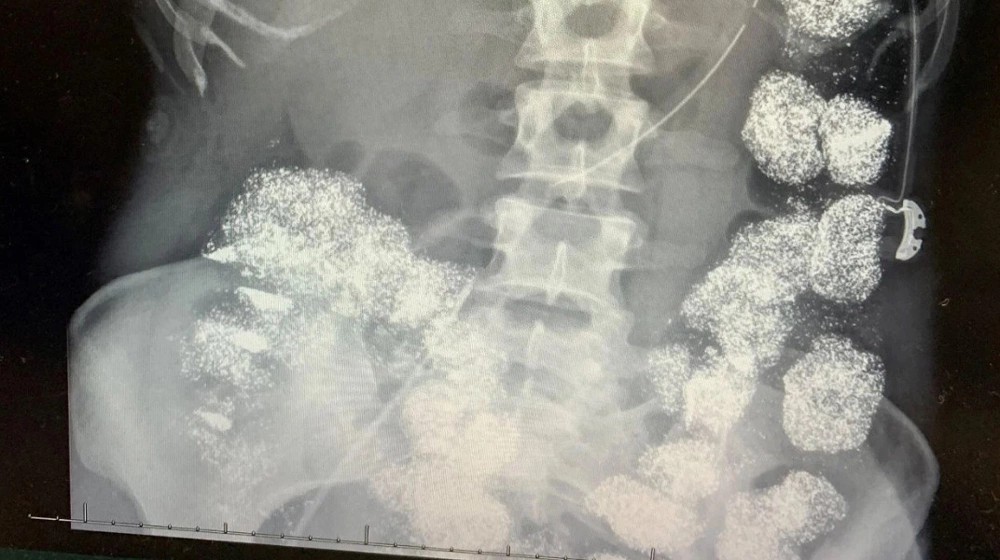

Mọi nghi ngờ bùng nổ khi xét nghiệm máu cho thấy nồng độ chì trong cơ thể Hannah vượt quá 80 mcg/dL, cao gấp 8 lần ngưỡng an toàn. Chụp X-quang phát hiện kim loại nặng phủ kín dạ dày, đại tràng và đã ngấm vào xương.

Hình ảnh X-quang cho thấy cơ thể Hannah Pettey bị lấp đầy bởi chì. Ảnh: Hartselle Police Department